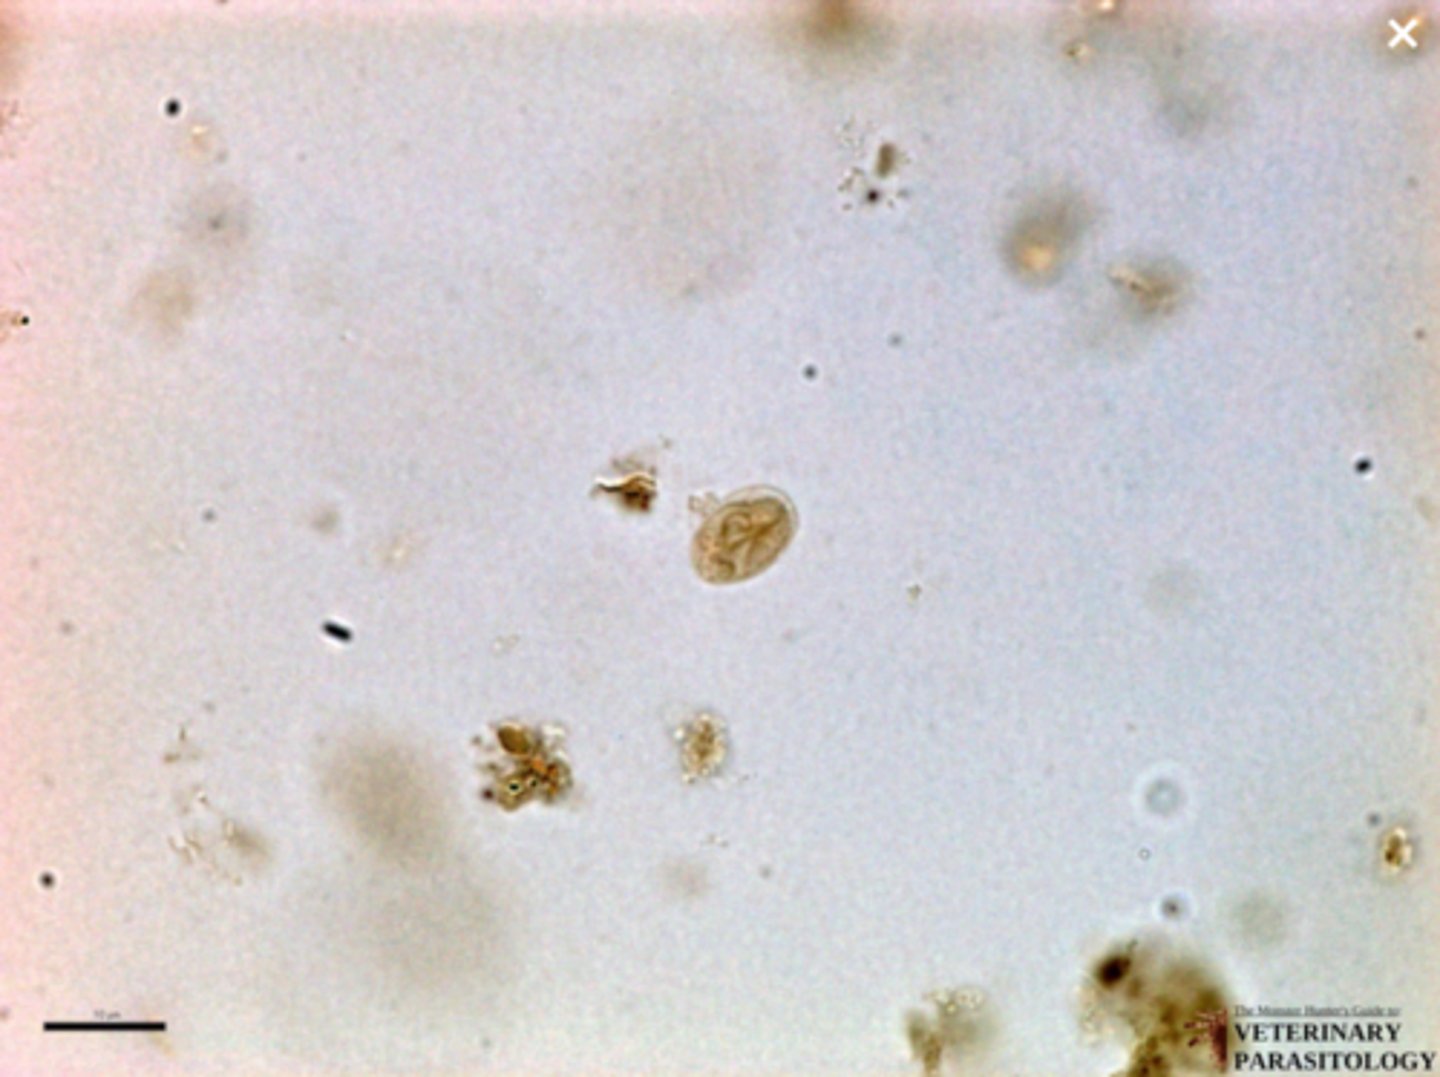

Giardia spp. (cyst) (critical error)

What parasite is this if it is from a dog

What parasite is this if it is from a cat

Giardia spp. (trophozoite) (critical error)